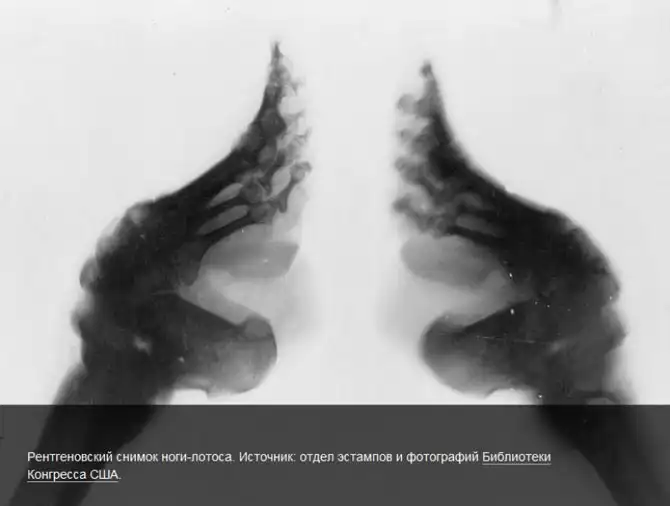

Ради красоты китаянкам приходилось идти на серьезные жертвы: с начала X до начала XX века в стране был популярен культ изящной ножки. Верхом изящества считалась стопа длиной 10 см, изогнутая в форме полумесяца и напоминающая лотос. Для достижения такого эффекта девочкам в 4-летнем возрасте перебинтовывали ступню таким образом, чтобы четыре пальца сгибались и соприкасались с подошвой. В таком положении стопа переставала расти и деформировалась. Маленькая, напоминающая копытце ножка считалась символом женского целомудрия и самой привлекательной частью женского тела. Красотки с забинтованными ногами с трудом передвигались, хромали и испытывали боль при ходьбе. Зато шансы благополучно выйти замуж у обладательниц лотосовых ножек были гораздо выше. В начале XX века нога-лотос вышла из моды, и китаянки перестали страдать из-за этого канона красоты.